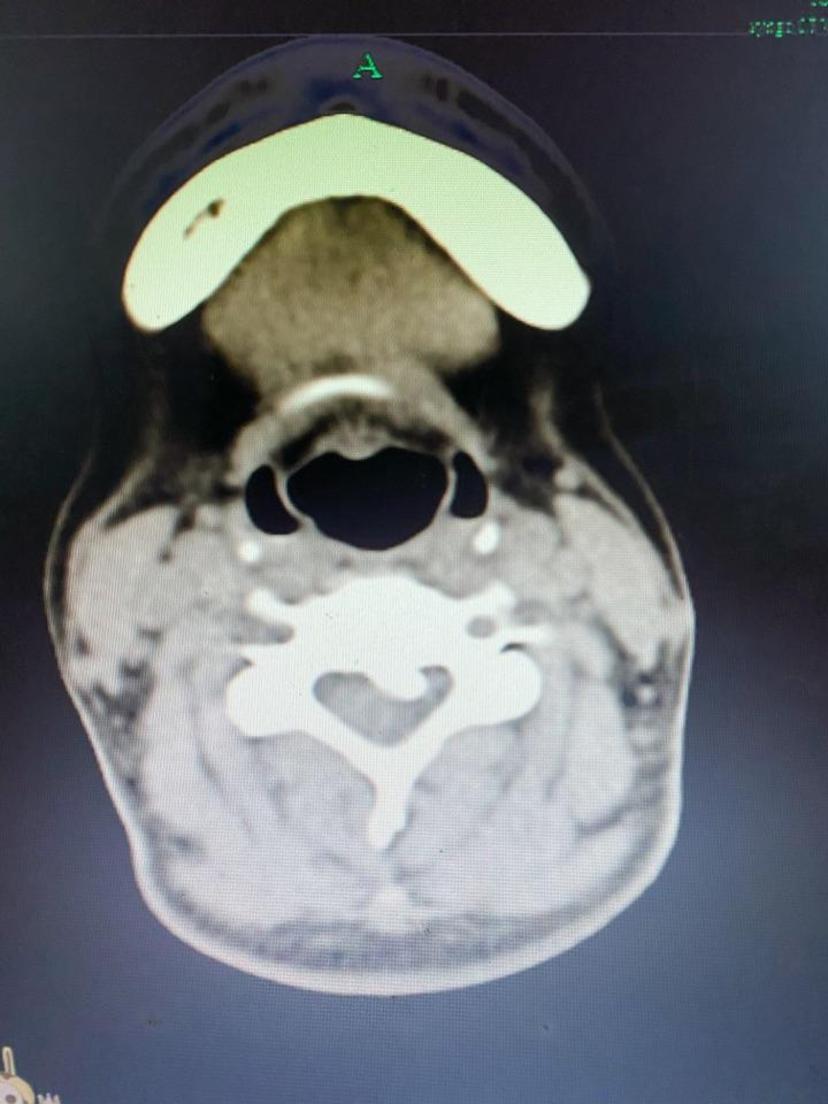

突起的骨化物

顺利取出压迫神经脊髓的椎间盘及骨化物